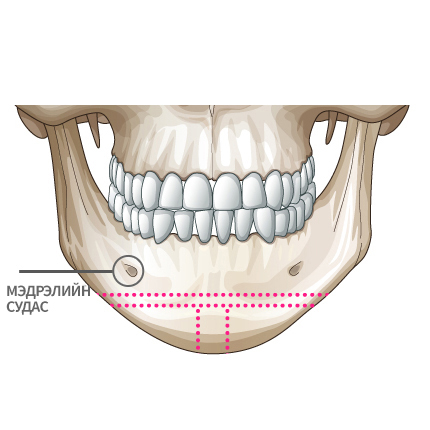

Mini V-line мэс заслын арга

Мэдрэлийн судаснаас зайлсхийж, эрүүний төгсгөлд зүсэлт хийнэ.

Ясны гол хэсгээс тайралт хийж авна.

Зүсэлт хийгдсэн эрүүний хоёр талыг нийлүүлнэ.

Эрүүний ясыг нийлүүлж тогтоож өгнө.

Хоёр хажуу талд товойж харагдах ясны хэсгийг тайрна.